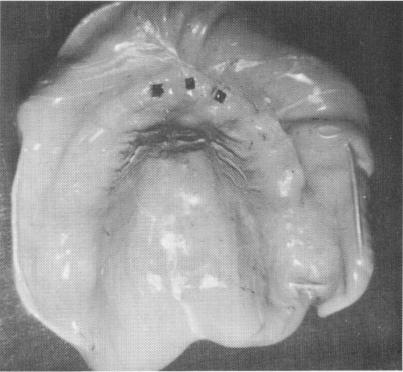

Fig. 10-231. Three vent-plants are placed in the incisor region.

1 Three ventplants placed in maxillary incisor region